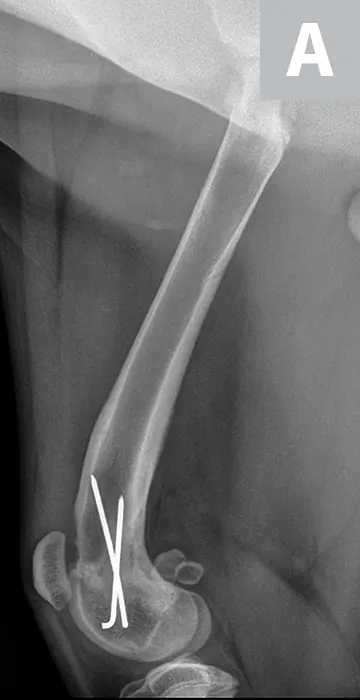

Maggie was managed overnight with analgesia (ie, hydromorphone [0.05 mg/kg IV q4-6h]) and nursing care. The following morning, Maggie was placed under general anesthesia and given a morphine epidural, and surgical fixation of the fracture was performed through a craniolateral approach to the stifle. The distal femoral physis is W-shaped and has inherent stability when reduced; however, additional stabilization is required to provide adequate resistance to the forces applied across the fracture and to allow for the stability needed for healing. Two smooth pins were placed obliquely across the fracture site (Figure 2). The pins should cross proximal to the fracture site to provide maximal repair stability.7

Figure 2

Lateral (A) and craniocaudal (B) radiographs of the femur immediately after open reduction and internal fixation with 2 cross pins. The pins cross proximal to the fracture site, which is important for stability of the repair.